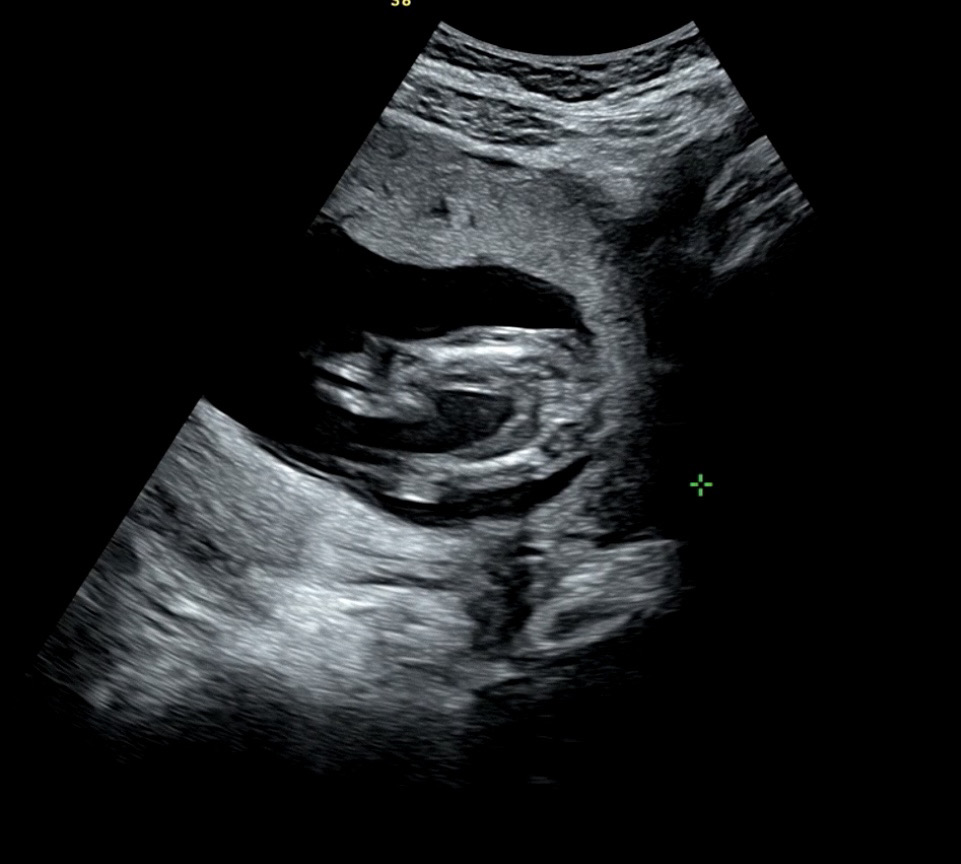

16주 성별 반전 있을까요?!

12주, 14주 초음파 때부터 딸 같다고 하셨고 오늘 16주 초음파에서도 딸인 것 같다고 하셨는데요 그래도 20주 정밀초음파가 제일 정확할 거라고 그러셔서 떨리네요 성별 반전 가능성 있을까요??? 양가 어른들께 알려도 될지 궁금해요 얼른 말하고 싶어서..ㅎㅎㅎ

딸같어요! 13주차에 가랑이사이에 아무것두 없엇는데 딸이엿어요!

저 방금 초음파보러다녀왓는데요! 15주차인데 딸에서 아들반전 없을거라고 하시더라구요!! 저도궁금해서 물어봣어요!! 안심하라고 하셨어요

딸같은데용?